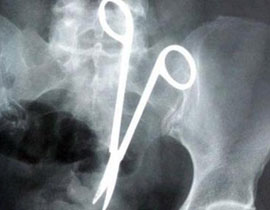

وبالذهاب إلى طبيب آخر، والذي طلب من المجني عليه إجراء إشعاعات مقطعية على البطن، والتي تبين من خلالها وجود مقص داخل البطن، حسبما ذكرت صحيفة "الشروق".

وقد تم تحويل المجني عليه إلى الطب الشرعي، والذي أثبت صحة البلاغ ووجود مقص داخل بطنه، تم ضبط وإحضار الطبيب، وبمواجهته اعترف بالواقعة.